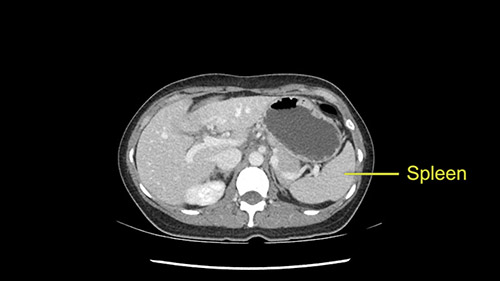

As I review the CT scan, we have both arterial and venous phases, the tumor is obvious. But I’ll start by saying that the liver itself does not appear to be cirrhotic to my eye. It’s got a normal contour and allied to that, that I do not see evidence of portal hypertension. The spleen is normal, there’s no collateral vessels. The tumor itself, I measured maximally at about 11 centimetres in diameter and I’m told the alpha fetoprotein is very high (over 10000), which is entirely consistent with this being a solitary hepatocellular carcinoma that is very exophytic. It seems to emanate off the inferior margin of Segment 3 (because that’s the falciform). I’ll start by saying that this is not transplantable. The tumor exceeds our guidelines for transplantation, but it's likely resectable based on normal liver and no portal hypertension.

So in planning for this operation, as I look at the scans, I first visualize the arterial phase and I can see that there’s are a lot of big feeding arteries to this large tumor. Likely all the right side vessels feeding the right side of the liver: right hepatic artery and likely the Segment 4 artery are spared from the tumor. It’s likely the left hepatic artery is ramificating and giving feeding arteries to this tumor. It certainly looks like a large mass that its compressing other structures like the cava, the pancreas, the stomach; but I think there’s a plane and we can see that better in the venous phase. There’s a plane of separation between the gallbladder, the pancreas, the cava, that this tumor is abrupting but likely not invading. Usually, these masses actually don’t invade at that level and basically are pushing the tissues and once you open, you’re able to separate the tumor. Sometimes there’s some adhesions but you can actually separate and there’s usually no invasion.